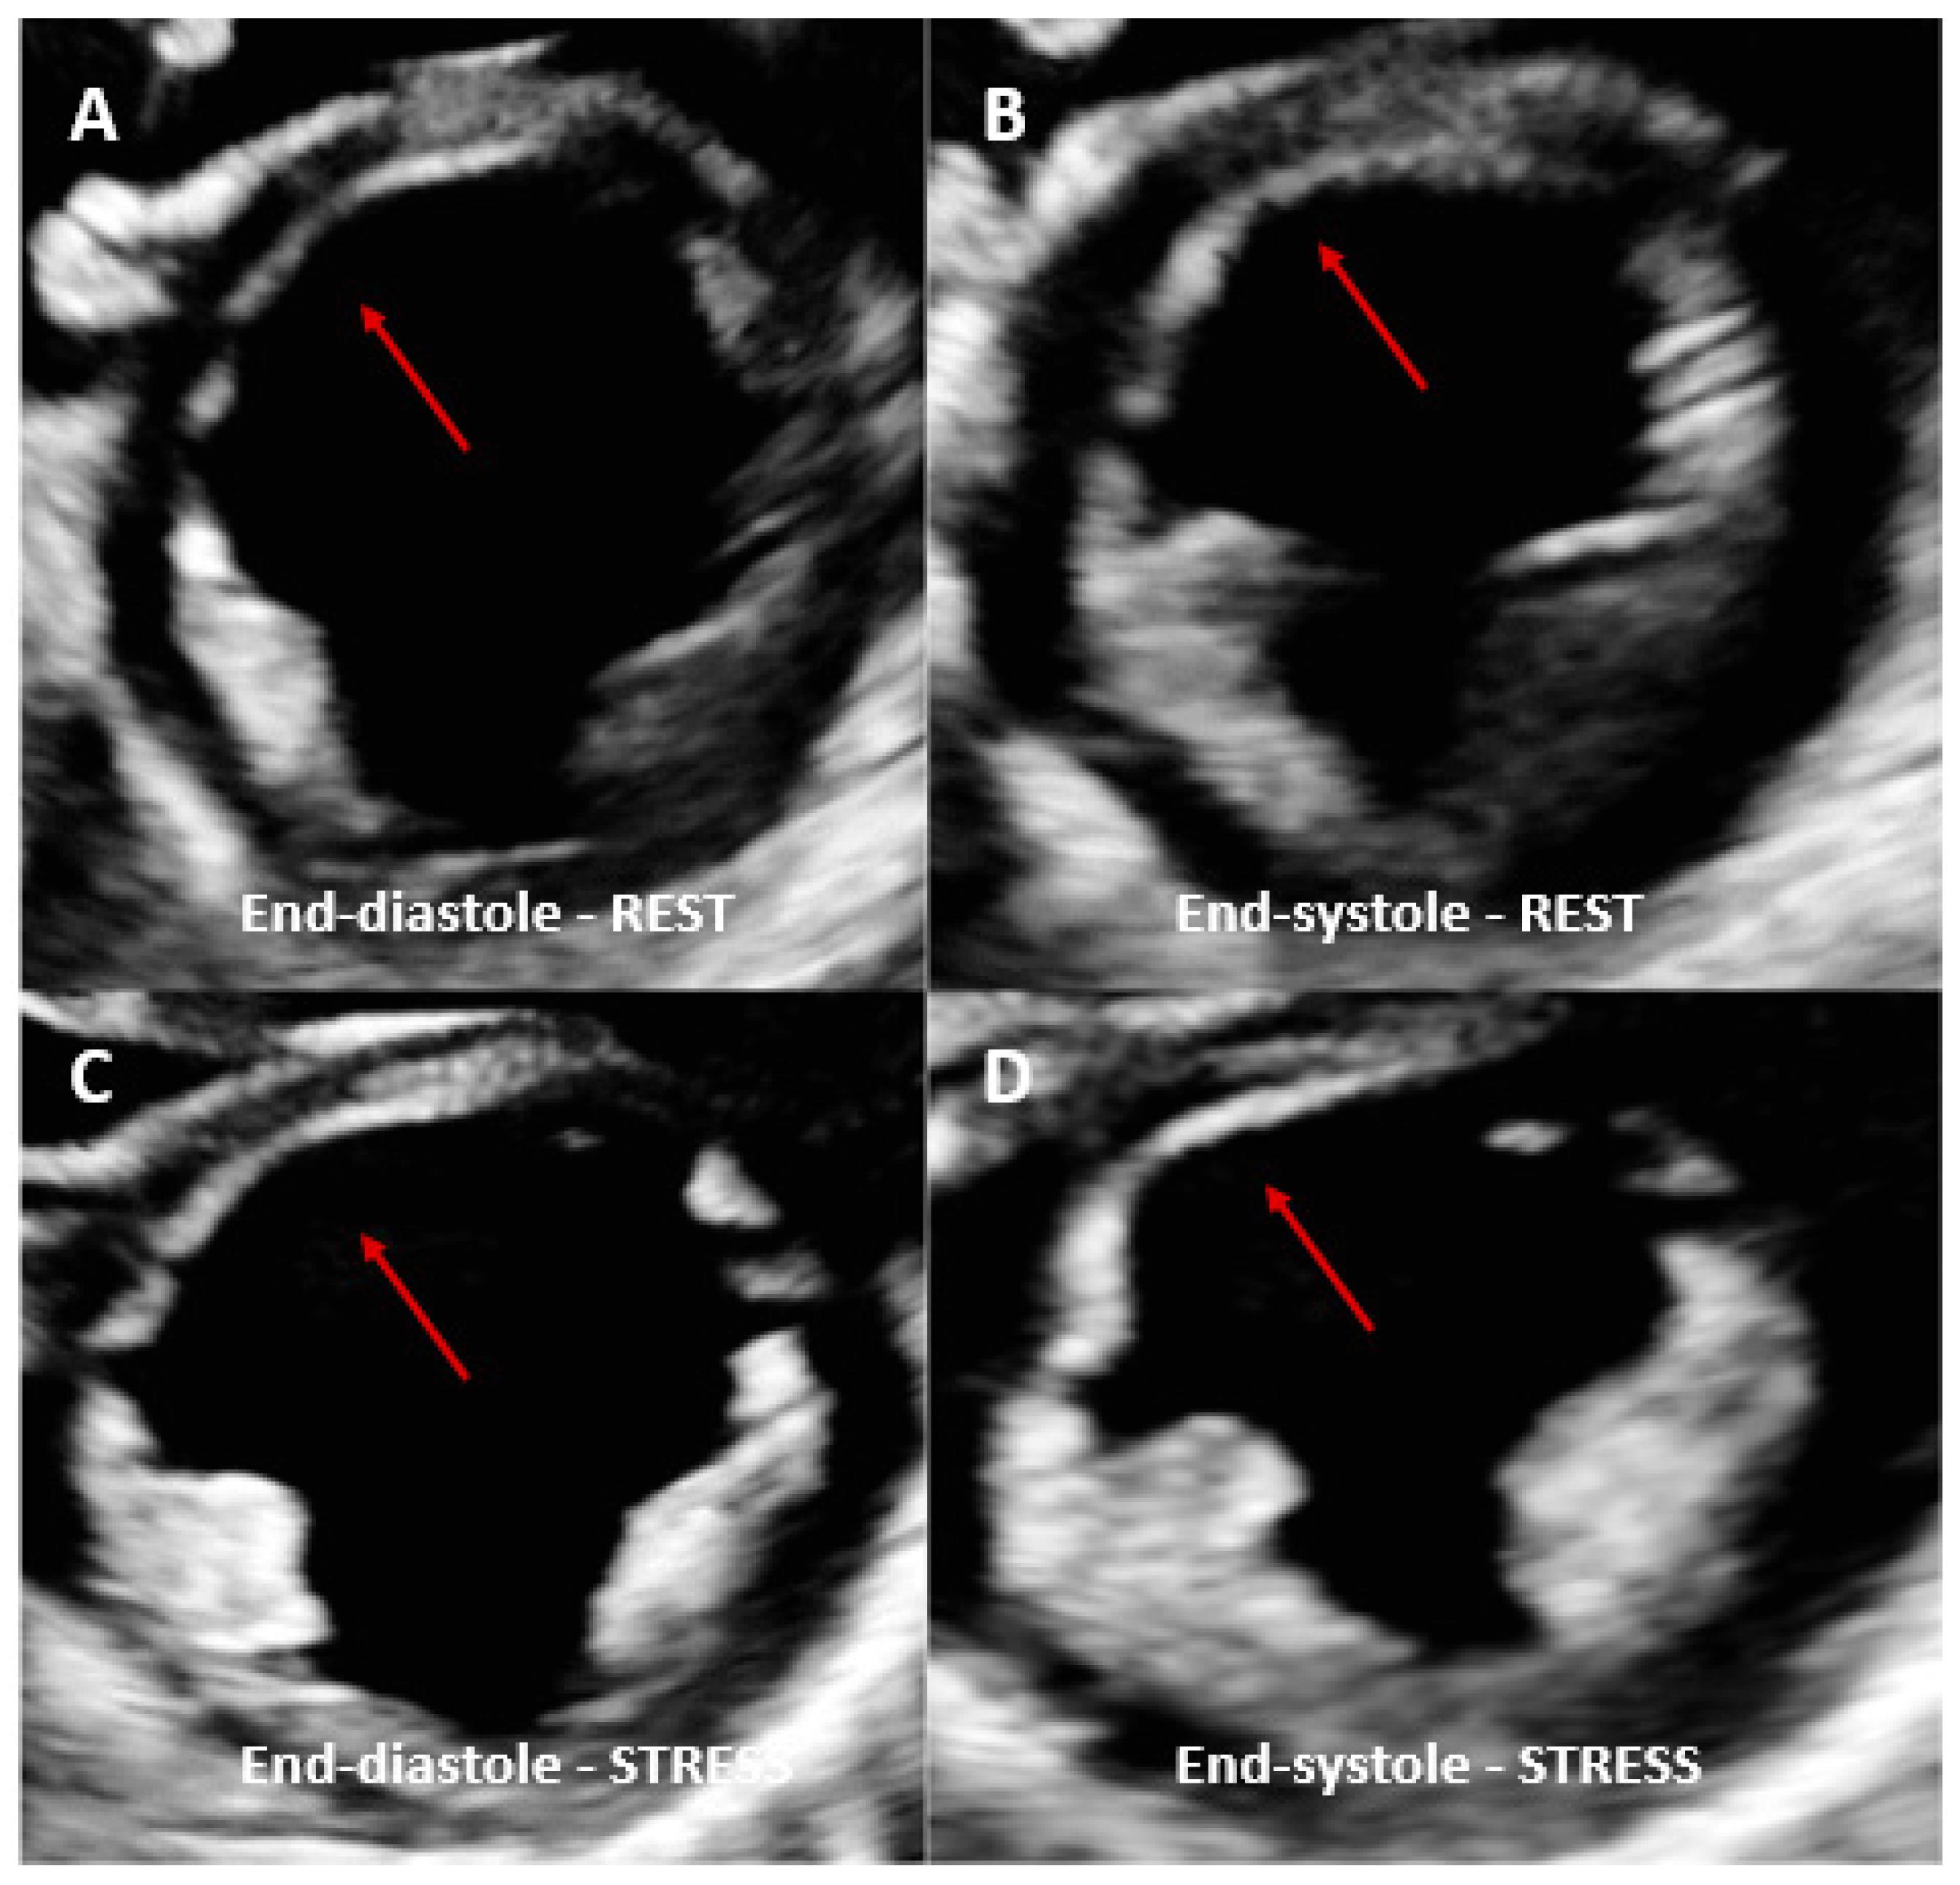

2. Stress Echocardiography

2.1. Introduction

2.2. Type of Stress Agents

2.3. Protocols

- Hui, L.; Chau, A.K.T.; Leung, M.P.; Chiu, C.S.W.; Cheung, Y.F. Assessment of left ventricular function long term after arterial switch operation for transposition of the great arteries by dobutamine stress echocardiography. Heart 2005, 91, 68–72. [Google Scholar] [CrossRef]